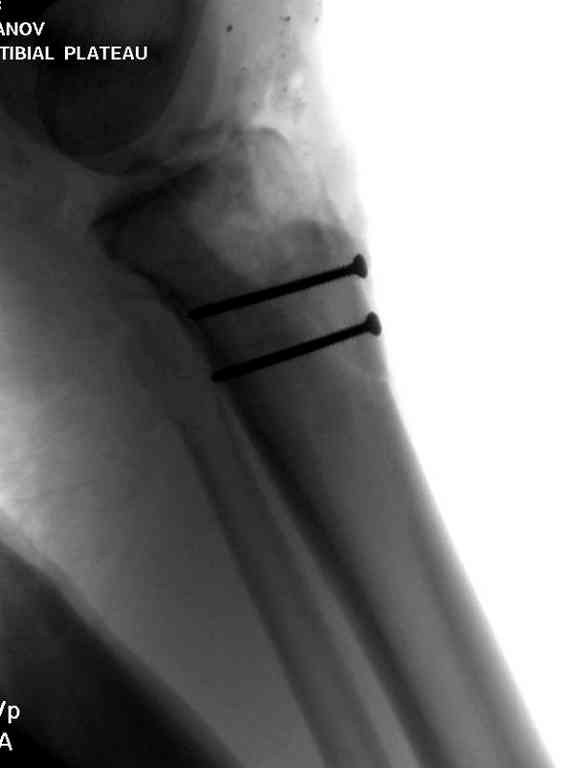

После нескольких обработок и вакуумирования, поэтапно сделана фиксация тибиального бугра шурупами. И окончательную фиксацию закончили латеральной пластиной для тибиал плато и установкой пластического материала.

Для закрытия мягкотканых дефектов привлечена другая служба.